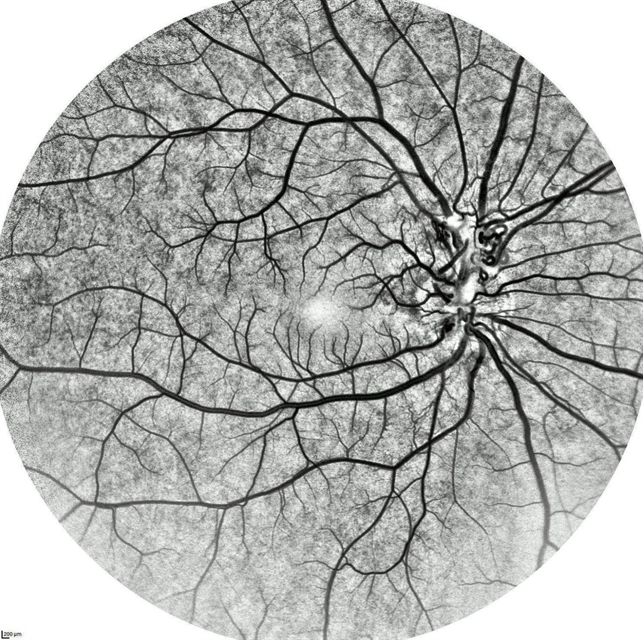

- congenital prepapillary vascular loop, pediatic retina

- Inverted FA of a 10-year-old boy with congenital peripapillary vascular loop.